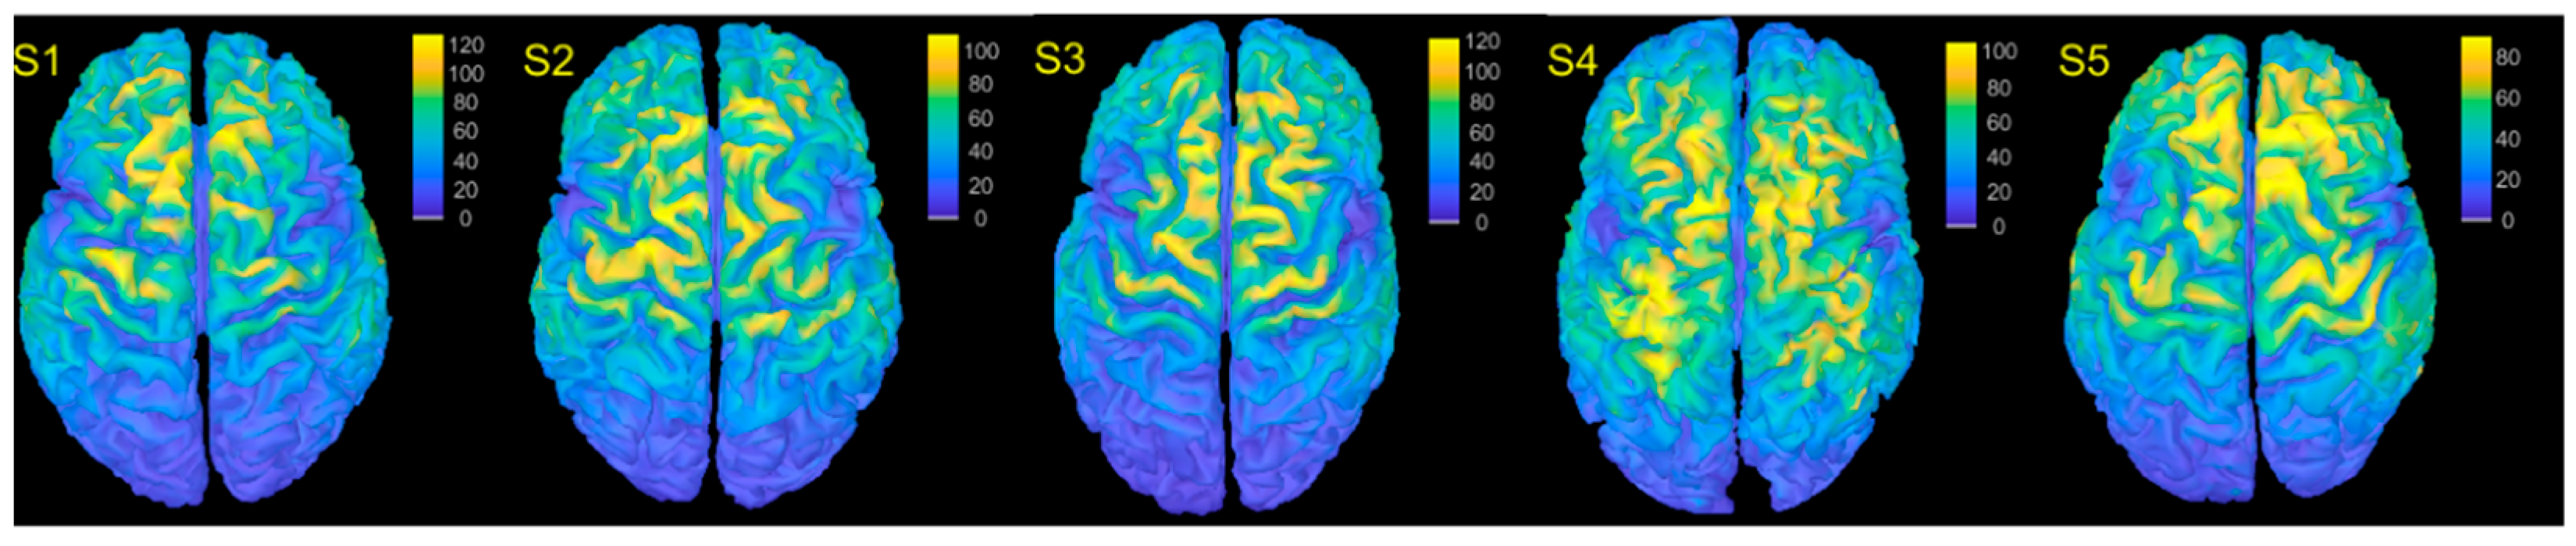

The computational models were employed to estimate the E-field intensity on the cortex for TMS stimulation equal to 120% of the LT (Figure 1). The stimulus intensity for each subject S1–S5 was respectively 38%, 36%, 36%, 34% and 32% of the MSO, the maximum E-field value was 127, 115, 121, 105, and 90 V/m2 and the average E-field was 33, 27, 29, 29, and 27 V/m2. The similarity between the computed E-fields was assessed by averaging the field values per Brodmann area and then estimating the Pearsons’ correlation. The average correlation was 0.94, while the minimum and maximum correlation values were 0.86 (S4–S5) and 0.97 (S1–S3), indicating a high similarity of E-fields on average, but with substantial case-to-case variability.

Figure 1.

E-fields for all subjects. Warm colors indicate high values, while cold indicate low values. The color scale is not consistent across subjects for visualization purposes.